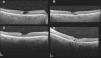

MethodsA retrospective study was conducted on the 12 eyes of 6 patients with MacTel 2. Fundus color photographs, fundus autofluorescence, fluorescein angiography, optical coherence tomography (OCT), and OCT-angiography were performed and subsequently analyzed. Visual acuity (VA) was prospectively recorded. The prevalence was established based on the patients referred to a specialized macular diseases unit. Minimum follow-up period was 18 months.

ResultsPrevalence of MacTel 2 in our study was 0.12%. Clinical features were presented using multimodal retinal imaging. VA remained stable during follow-up. Three patients developed choroidal neovascularisation (CNV), requiring intravitreal treatment with antiangiogenic agents.